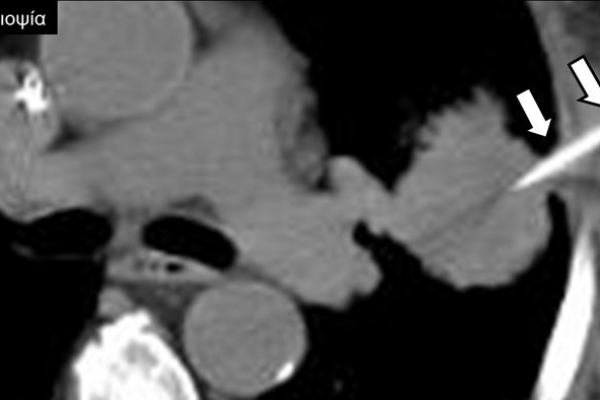

Η διαδερμική βιοψία είναι μία ελάχιστα επεμβατική μέθοδος λήψης υλικού από τον όγκο για κυτταρολογική και ιστολογική εξέταση, από εστιακές αλλοιώσεις του ήπατος, πνεύμονα, νεφρού κλπ. Συστήνεται από τον κλινικό ιατρό ανάλογα με το είδος και το μέγεθος της βλάβης και πραγματοποιείται με ασφάλεια από επεμβατικό ακτινολόγο με την καθοδήγηση αξονικού τομογράφου ή υπερήχων. Στη σύγχρονη ογκολογική θεραπεία όπου γίνεται προσπάθεια καταπολέμησης του καρκίνου σε μοριακό επίπεδο κρίνεται αναγκαία η ακριβής ιστολογική ταυτοποίηση του όγκου ώστε να εφαρμοσθεί εξατομικευμένη θεραπεία για το βέλτιστο αποτέλεσμα. Οι κατευθυνόμενες βιοψίες στοχευουν στο να παρέχουν στον κλινικό ογκολόγο το απαραίτο ιστοπαθολογικό υλικό που θα του επιτρέψει να εφαρμόσει την κατάλληλη θεραπεία για τον ογκολογικό ασθενή.